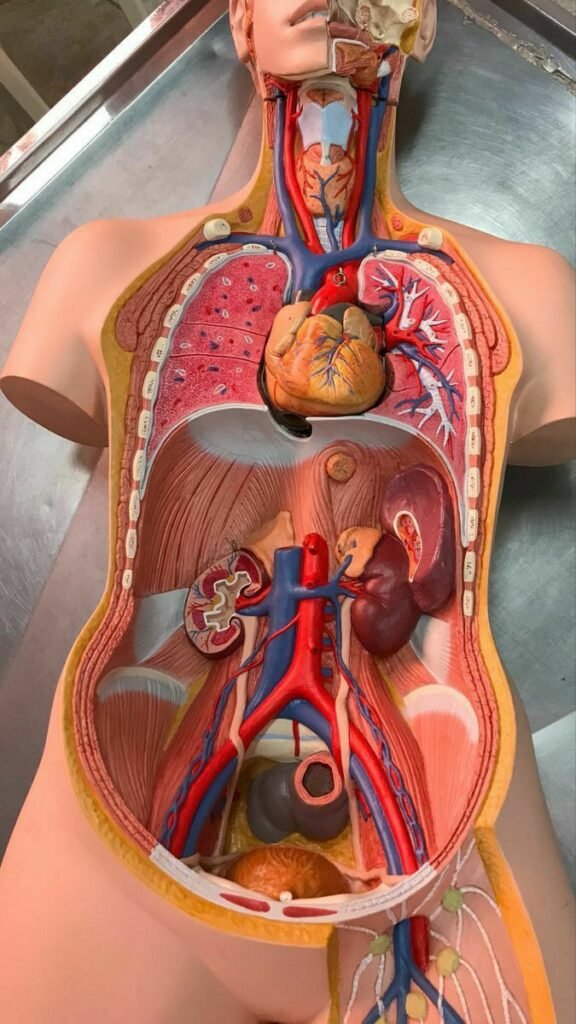

Antes de cumplir 13 años falleció mi abuela debido a una enfermedad cardiaca, al ver la tristeza e impotencia de mis familiares empecé a descubrir mi gusto por el área de la salud más que todo en la especialidad de cardiología y mi sueño pasó a ser convertirme en cirujana cardiovascular y sé que me esforzaré mucho para lograr este objetivo.